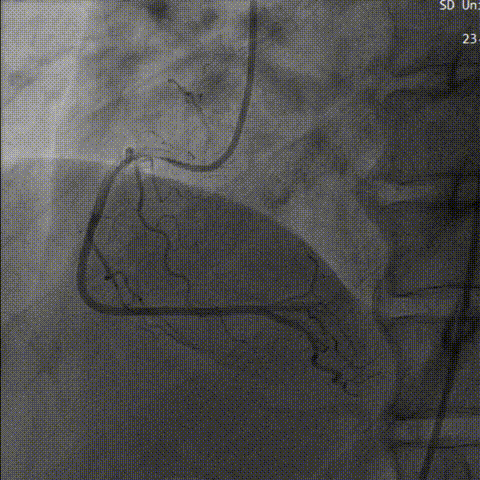

行主动脉根部造影,猪尾确定选择最佳释放体位,观察瓣叶活动,确认是否合并反流,选择合适体位跨瓣。

主动脉根部造影